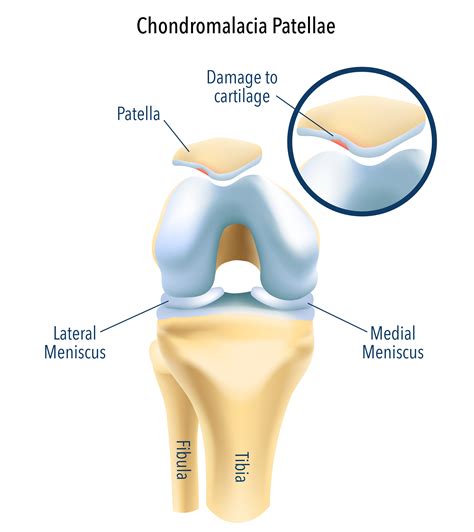

Patella Alta, also known as a high-riding patella, occurs when the kneecap is positioned abnormally high in the knee joint. This condition can lead to various issues, including pain, instability, and difficulty in performing daily activities. The primary cause of Patella Alta is often related to anatomical abnormalities, such as a shallow trochlear groove or a long patellar tendon. Other factors, such as previous knee injuries or surgeries, can also contribute to the development of this condition.

Diagnosing Patella Alta

Diagnosing Patella Alta involves a combination of physical examination and imaging tests. A healthcare professional will typically perform the following steps:

• Physical Examination: Assessing the knee for signs of swelling, tenderness, and range of motion. The healthcare provider may also perform specific tests to evaluate the stability and alignment of the patella.

• Imaging Tests: X-rays, MRI, or CT scans to visualize the position of the patella and identify any underlying structural abnormalities.